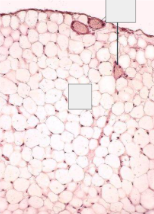

Adipose Connective Tissue